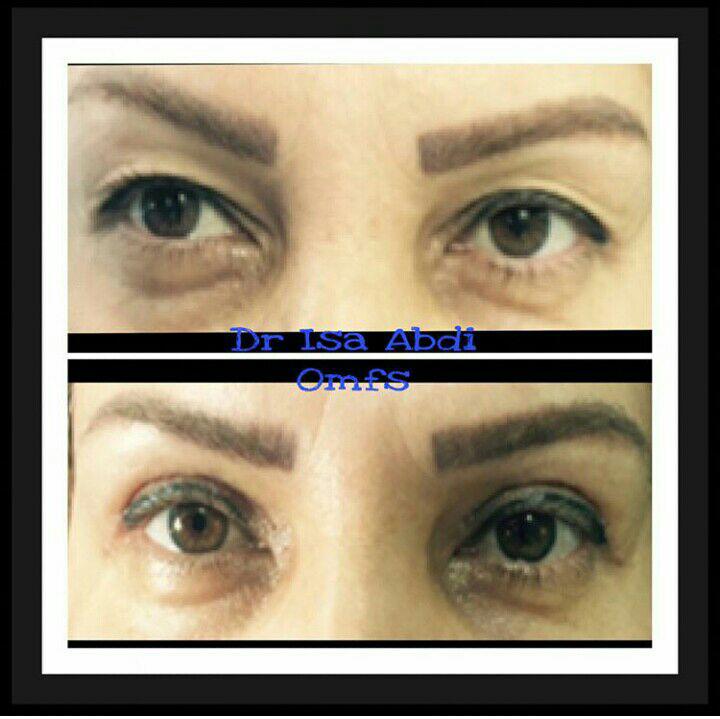

دکتر عیسی عبدی در رشت

دکتر عیسی عبدی در رشت

– متخصص جراحی فک , پلاستیک صورت و بینی

دکتر عیسی عبدی در رشت

تزریق ژل و بوتاکس